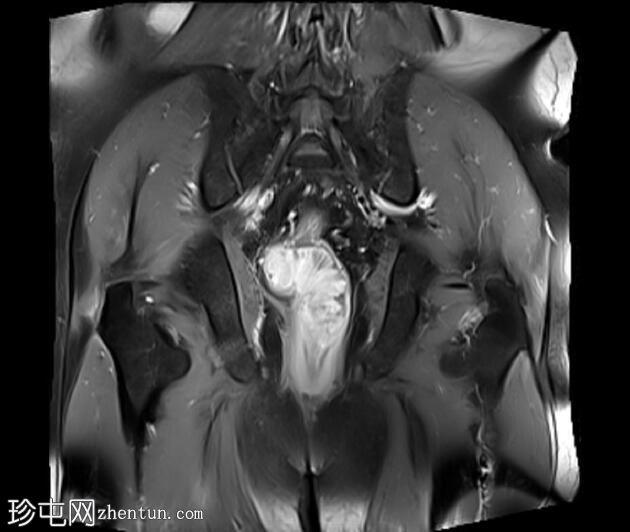

冠状位PD加权像

脂肪抑制像

可见一不规则分叶状肿块,累及直肠中段和远端,头尾方向长约7 cm,下缘距肛缘约2.5 cm。在T1加权像和T2加权像上,该病灶相对于骨骼肌均呈高信号。 PDFS(脂肪抑制)图像显示持续高信号强度,提示存在黑色素和/或出血成分。

增强扫描显示病灶内呈不均匀强化。直肠下段7点钟位置的系膜筋膜受累。后方系膜可见少量淋巴结。未见邻近器官侵犯。